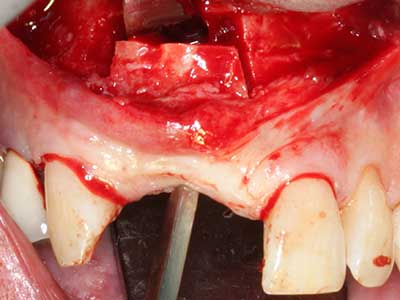

La preparación de la ventana lateral en la elevación del suelo del seno maxilar representa un enorme reto, sobre todo para profesionales de la implantalogía que tienen poca experiencia en técnicas quirúrgicas. Retirar la cobertura ósea del seno maxilar sin provocar daños en la membrana de Schneider es tan solo una parte de la operación; tras crear un acceso suficiente, es preciso movilizar con cuidado la mucosa del seno maxilar a fin de dejar espacio para el material o los implantes que vayan a incorporarse. En esta aplicación la cirugía piezoeléctrica resulta útil en dos sentidos: por un lado, el uso de insertos diamantados permite realizar una retirada selectiva del hueso y, si se actúa con cuidado, la membrana permanece intacta, y por otro lado, las frecuencias de ultrasonidos favorecen también un desprendimiento sin problemas de la membrana, pues se transfieren al espacio comprendido entre la mucosa y el suelo del seno maxilar gracias al uso de piezas romas especiales (Cassetta, Ricci et al. 2012, Pereira, Gealh et al. 2014) (Rickert, Vissink et al. 2013). De este modo, no es de extrañar los trabajos publicados en la actualidad sobre la técnica de elevación del suelo del seno maxilar mediante la técnica de Caldwell-Luc con instrumentos piezoeléctricos (Wallace, Tarnow et al. 2012).

En la extracción de bloques óseos la piezocirugía también presenta ventajas adicionales: Además de la alta precisión en la osteotomía que ya se ha descrito antes, se ha comprobado que el uso de los delgados insertos de sierra resulta especialmente cuidadosas con el hueso. Frente a esto, sobre todo cuando se usan las fresas de Lindemann, cabe esperar pérdidas en la extracción significativamente más altas debido al mayor grosor de la parte frontal del cabezal (Lakshmiganthan, Gokulanathan et al. 2012). La separación basal que se necesita en particular en los injertos de bloque extraídos de forma retromolar se ve facilitada mediante sierras perpendiculares especialmente previstas a tal fin, lo que permite considerar que la cirugía piezoeléctrica es un procedimiento preciso y seguro para la obtención de bloques de hueso en el área retromolar (Happe 2007) (fig. 1-12).